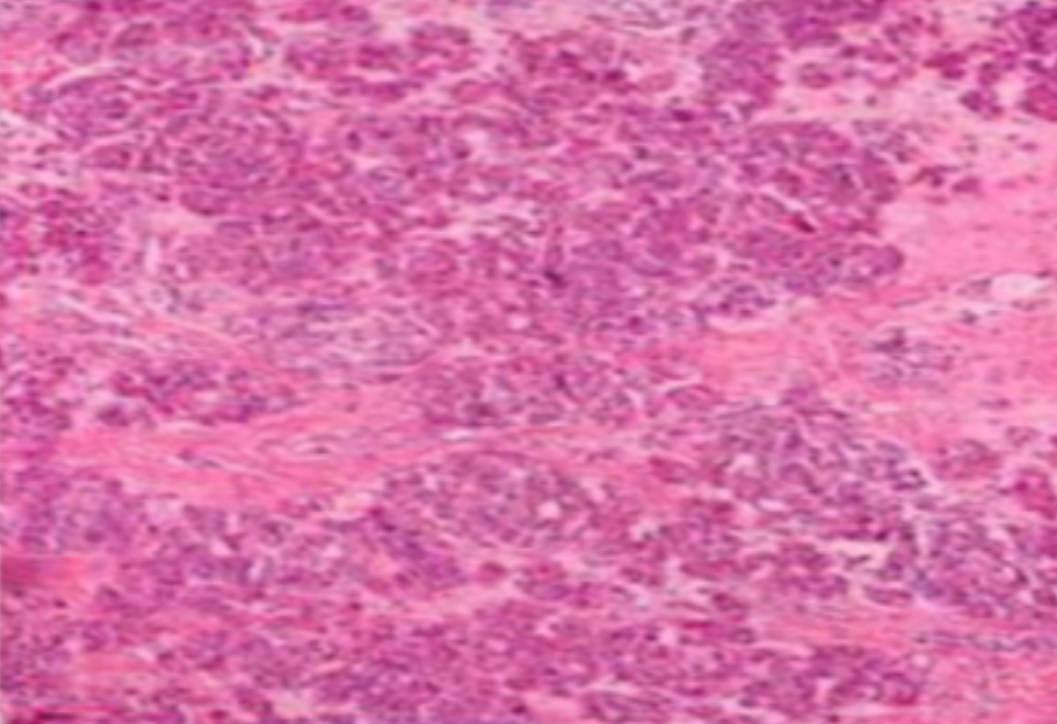

形成原因:切片经梯度乙醇处理后没有完全脱水,导致二甲苯透明、中性树胶封固后残留大量水分。 解决方法:首先移去盖玻片,用二甲苯溶解封固剂如中性树胶,再将切片置入无水乙醇内,待切片重新脱水完全后,用二甲苯透明处理,中性树胶封固。要注意所有用于脱水和透明的液体,在使用一定时间后,应及时更换。 二、细胞核呈红、棕色 形成原因:苏木精染色液过度氧化,切片在苏木精染液染色后返蓝不足。 解决方法:每次染色之前检查苏木精染色液的染色能力,发现苏木精染色液氧化过度应及时更换。此外,切片经苏木精染色后,要给切片以足够的蓝化时间,蓝化过程可用流水、温水、弱碱性溶液(如稀氨水或0.2%碳酸氢钠)等处理。 三、切片在脱蜡后出现大片白色斑点 形成原因:由于烤(烘)片温度太低,切片上的组织蜡膜在脱蜡前没有充分烤(烘)融化。或是因为切片在二甲苯液中停留时间不足,或二甲苯使用过久,造成的脱蜡不彻底。 解决方法:若是由于切片烤(烘)温度低所致,可以先用二甲苯去除切片上的封固胶,然后重新用二甲苯脱去切片上的石蜡,再进行后续染色。若是由于切片在脱蜡的二甲苯中停留时间不足或脱蜡二甲苯使用过久浓度不足所致,则需将切片退回到二甲苯中,停留较长时间,或更换二甲苯液体重新脱蜡,再入乙醇重新脱二甲苯,入0.5%盐酸水溶液褪色后,重新HE染色。 四、细胞核苍白暗淡,即苏木精染色太淡 形成原因:切片在苏木精染色液停留时间太短;苏木精染色液过度氧化,失去染色能力,不能再继续使用;分化步骤处理时间过长;固定不及时。此外值得注意的是,若骨组织细胞核暗淡,大多是脱钙过度造成的。 解决方法:切片重新染色。如果组织在酸性固定液(如Zenker、Bouin)或非中性缓冲甲醛液固定时间过长,细胞核染色能力将减弱,需增加其在苏木精染色液的时间,或用一些方法增加组织的嗜碱性,以改善细胞核的着色。例如,上述组织玻片可以使用Weigert铁苏木精染色液。如果组织是用Zenker液固定的,可将切片脱蜡后放在5%碳酸氢钠溶液3~4h,流水冲洗5min后染色。如果组织是用Bouin液固定的,可将切片脱蜡后放在5%碳酸锂1h,流水冲洗10min后染色。 五、细胞核过染,苏木精染液占据了细胞质 形成原因:玻片在苏木精染色液停留时间过长,或是切片太厚、分化步骤时间太短。 解决方法:如果不是因为切片太厚(用显微镜仔细上下微调,只有一二层细胞核层次),就需将切片进行脱色、漂白、重新染色,适当调整染色和分化时间。但如果确定是由于切片太厚导致的细胞核过染,则需要重新切片。 六、伊红着色淡 形成原因:可能是伊红染液pH值大于5,也可能是蓝化液残留过多,切片太薄,或是切片经伊红染色后在乙醇脱水时间过长。 解决方法:检查伊红染液pH值,必要的话,用乙酸将其调节在4.6~5.0之间,从而使伊红染色色彩艳丽。此外,确保每次蓝化步骤完成后,使用的弱碱性溶液被充分洗去,玻片上没有残留的弱碱性溶液。最后,检查切片的厚度,且脱水时不要让切片在低浓度乙醇中停留时间过长,因为含水多的低浓度乙醇会将切片伊红的颜色分化掉。 七、细胞质过染、分色不足 形成原因:伊红染色液浓度太高,特别是存在焰红燃料、四溴四氯荧光素钠。切片在伊红染色时间过长,或是切片在伊红染色后经乙醇脱水步骤时时间太短,而使乙醇分化伊红的作用不能产生,都能够使细胞质过染。 解决方法:适当稀释伊红染色液,减少伊红染色时间,或使切片在乙醇脱水等步骤时,停留时间相对均匀。同样,也要检查切片的厚度是否合适。 八、切片中出现蓝黑色沉淀物 形成原因:苏木精染色液中的金属膜黏附在玻片上。 解决方法:染色前仔细过滤苏木精染色液,建议使用半氧化苏木精染色液,如Gill苏木精染色液,可以避免过多的金属膜产生。 九、光镜下切片某些区域难以聚焦 形成原因:盖玻片上可能有封固切片的封固剂。 解决方法:移去盖玻片,重新用干净的盖玻片封片。检查切片封片方法,是人工手工封法,还是机器自动封法,如有问题及时调整。 十、封固剂从盖玻片与载玻片之间的缝隙回缩 形成原因:盖玻片弯曲或不平整,或是封固剂含二甲苯过多,稀释过度。 解决方法:移去盖玻片,重新找一张盖玻片,用干净的封固剂封片。如用手工封片法,保证在封固结束时,封固剂容器盖子为紧闭状态。且尽量使用小的容器盛装封固剂,一旦封固剂太黏稠,就可以选择废弃。 十一、细胞核呈灰蓝状态 形成原因:可能由于组织处理温度过高、过热,在液体石蜡中停留的时间过长。或是固定时间太短后,直接在高浓度的乙醇中进行了脱水处理。 解决方法:理论上来说,仅在组织浸蜡步骤才进行加热,组织不能在热蜡液中停留太久。如果由于某些原因不能进行下一步包埋处理,可将组织连同塑料包埋盒一并放置在室温空气中,冷却凝固,以备包埋。待需要包埋时再重新加温直至石蜡融化即可。组织在处理前必须确保固定良好,脱水最好能从低浓度的乙醇开始。 十二、类色素的点状结晶和黑色光滑细胞核 形成原因:这种裸核改变是因为切片封片前放置在空气中的时间太长,以至于二甲苯挥发,切片干燥。 解决方法:移去组织切片上的盖玻片和封固剂,重新处理。将切片水洗数分钟,然后重新脱水、透明、封固。封片过程中要保持组织切片的轻度湿润,尽量不要让其干燥。 十三、染色过淡或过浓 解决方法:如果染色过淡,可以增加染色剂的浓度、延长染色时间或更换新鲜的染色剂;如果染色过浓,则应减少染色剂的浓度或缩短染色时间。 十四、切片出现叠加褶皱 形成原因:新购买的玻片洁净度不够、用镊子撑开切片时操作不够熟练未能平整伸展,或玻片表面有油脂,切片粘贴不牢。另外,烤片时间不足、烤片温度过低或切片过厚造成切片脱落,都会造成重叠或有皱褶的情况。 解决方法:新购买的玻片最好能用硫酸清洁液浸泡一晚,然后流水冲洗干净。在适宜的温度下烤片时间宁长勿短,保证有充足的烤片时间和温度。另外,切片刀要锋利,才能切出厚薄适宜的切片,保证切片不会因为过厚而脱落。 十五、组织残缺不全或有刮划痕迹 形成原因:组织残缺不全是由于切片时修整蜡块时深度不够、组织没有全部暴露于切面。切片的刮划痕迹是由于切片刀的刀锋有缺口、包埋的组织有异物,或是钙化组织、骨组织及包埋石蜡有沙粒造成的。 解决方法:修整蜡块时保证组织块全部暴露于切面,切片时保证切片刀的锋利没刀口。同时在组织取材时去除手术异物和钙化组织。最后,骨组织要完全脱钙,这样可以保证切片的完整和平整美观。 *注:由于实验中导致结果出现误差的原因多种多样,以上内容仅供参考,具体根据实际情况进行判断。